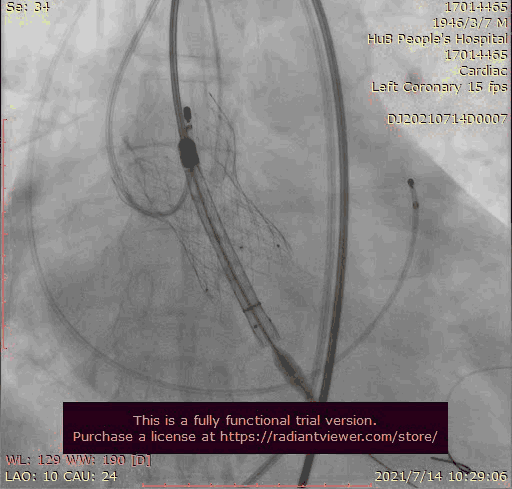

奇思妙想使用射频消融大头压住支架至窦底

在大头压迫支架下释放第二个瓣膜

第二个支架完美释放固定第一个支架

术后基本无返流